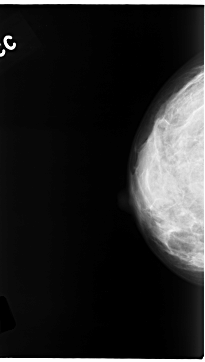

C_0139_1.RIGHT_CC

C_0139_1.LEFT_CC

LEFT_CC LINES 4704 PIXELS_PER_LINE 2624 BITS_PER_PIXEL 12 RESOLUTION 50 NON_OVERLAY